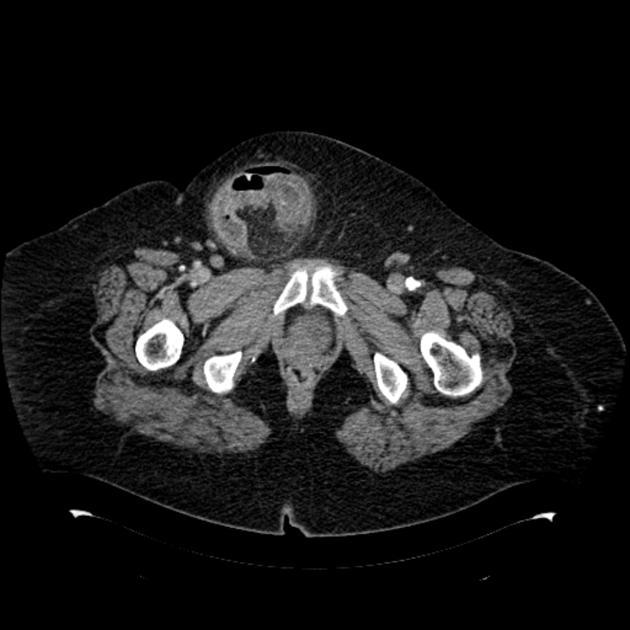

TDM TAP: diagnostic?

hernie inguinale étranglée. On voit une petite bulle d’air= nécrose pariétale